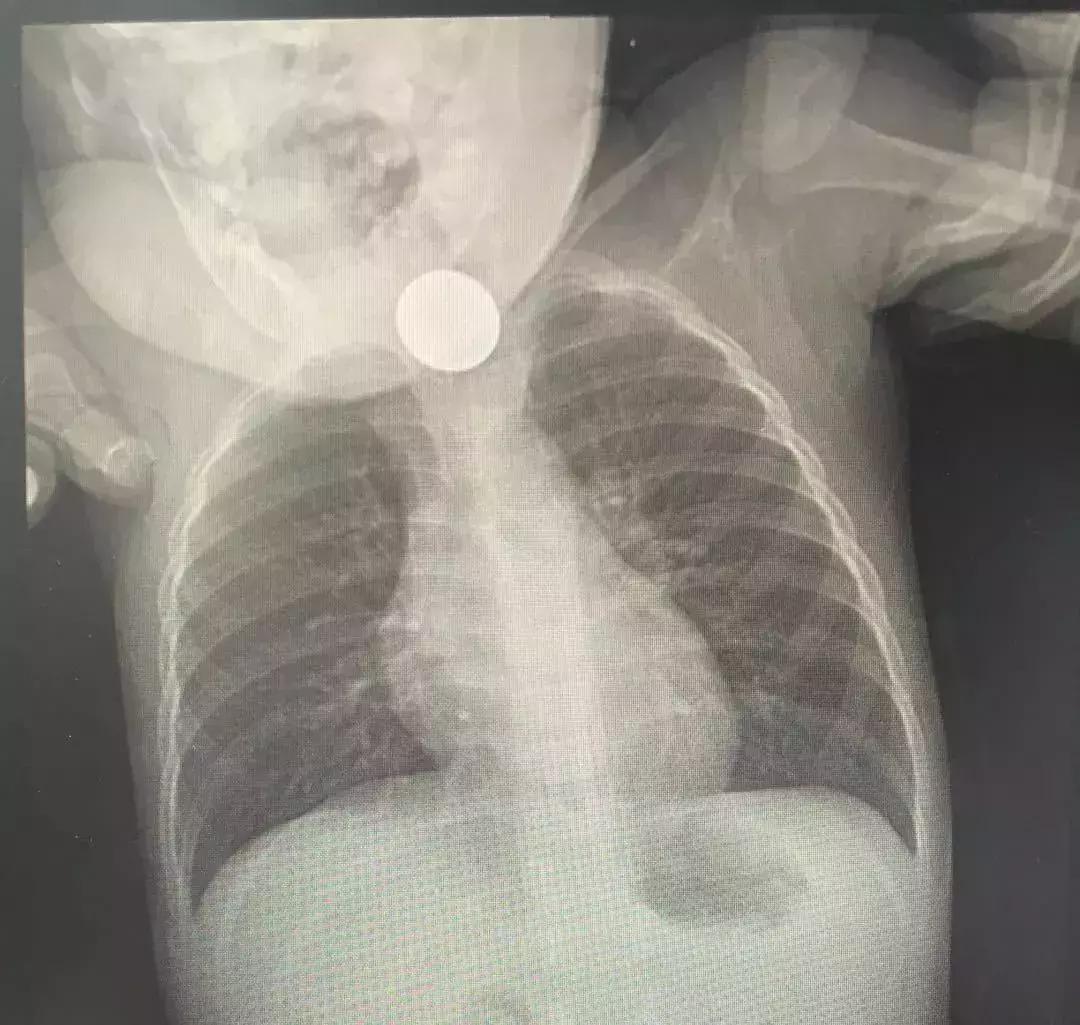

通过胸部X线显示,一枚直径约为21毫米的硬币卡在了心心的食管上端,接近食管入口。

“胸部X线显示硬币很大,内镜下看到已经把孩子的食道撑开很多,情况还是很危险的,如果长时间嵌顿可引起食道溃疡、穿孔等后果。幸好他们送来得早。”陈渭事后感叹。